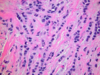

What is this?

Fibrocystic change: Bilateral, lumpy-bumpy, Blue domed cysts

What is this?

Fibrocystic change breast disease: Dilation of duct lobules, stromal fibrosis

What is this?

Fibrocystic changes breast disease: apocrine metaplasia

What is this?

Fibrocystic change breast disease: ductal ectasia